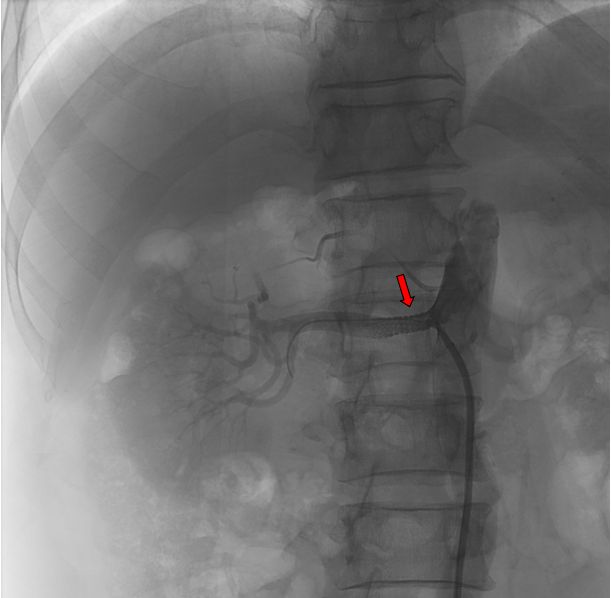

患者于4月9日上午送介入手术室行右肾动脉支架置入术。术中造影显示右肾动脉起始段明显狭窄,狭窄约90%,予置入肾动脉裸支架(7*19mm)后,造影显示右肾动脉狭窄解除,支架扩张良好,右肾灌注恢复。

图片 2.jpg

红色标记为支架置入前,右肾动脉明显狭窄